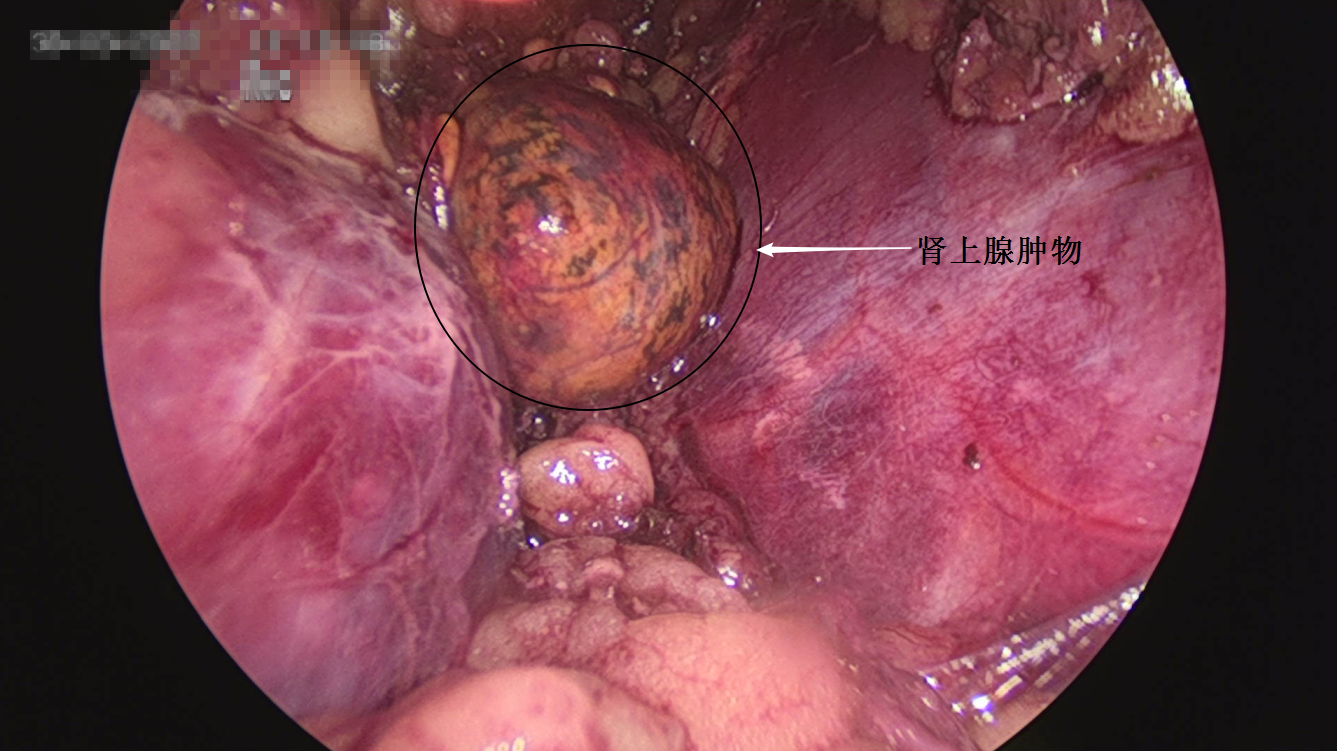

泌尿四科,通过详细检查后发现,刘女士的肾上腺上有个“鹌鹑蛋”大小的肿瘤,这个肿瘤分泌了大量的激素,引起身体代谢紊乱,这才导致了刘女士“满月脸”肥胖、高血压等症状。

经过精心术前准备,泌尿四科杨科主任为首的团队成功为刘女士在腹腔镜下实施了左侧肾上腺肿物切除术,目前刘女士的血压由入院时的220/130mmHg降至130/90mmHg左右,趋于正常,头晕、心慌症状也明显改善,激素替代疗法正在循序递减。